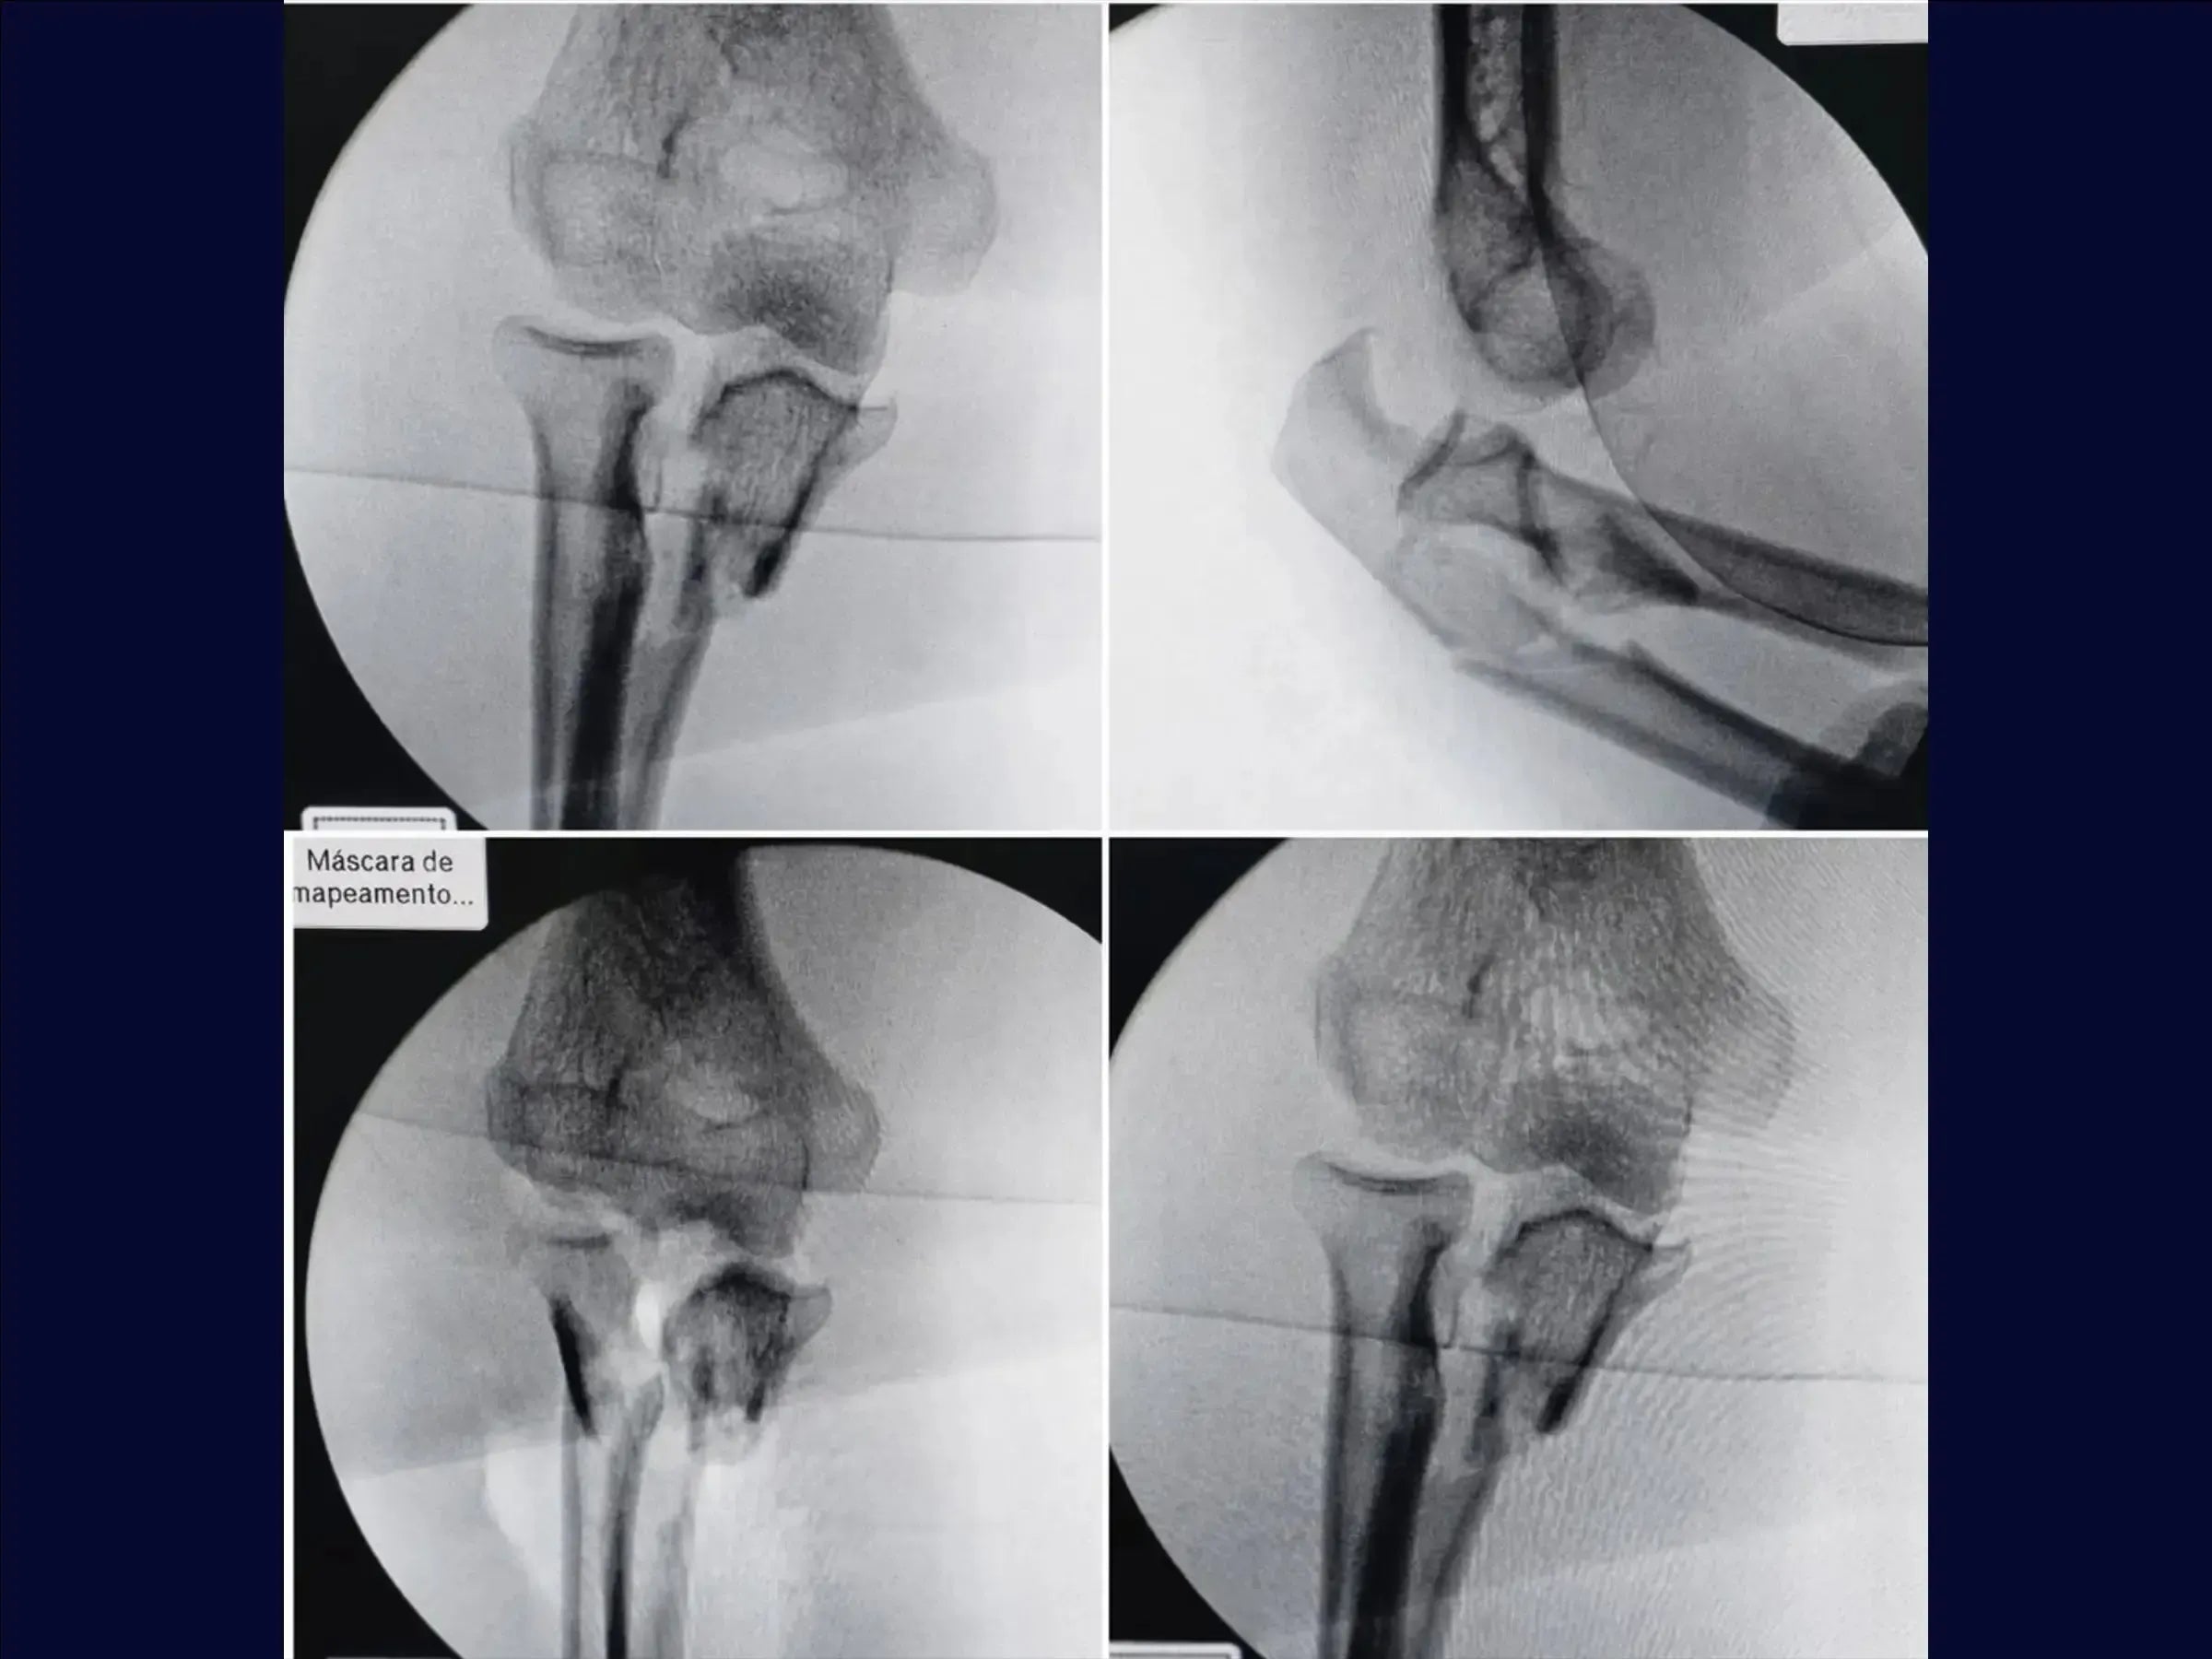

- Treatment of transolecranon fracture-dislocation of the elbow (Monteggia variant).

- Capsule Repair (Pull-Out Technique): Identification of the capsule and the coronoid process due to the fracture of the olecranon. Passage of high-strength wires and creation of tunnels to pull the capsule to the site of detachment, assisted by elbow flexion.

- Reduction of the Ulna: Fracture reduction with Kirschner wires.Lateral fragment fixation with a mini-fragment plate, enabling the use of a long plate on the olecranon.